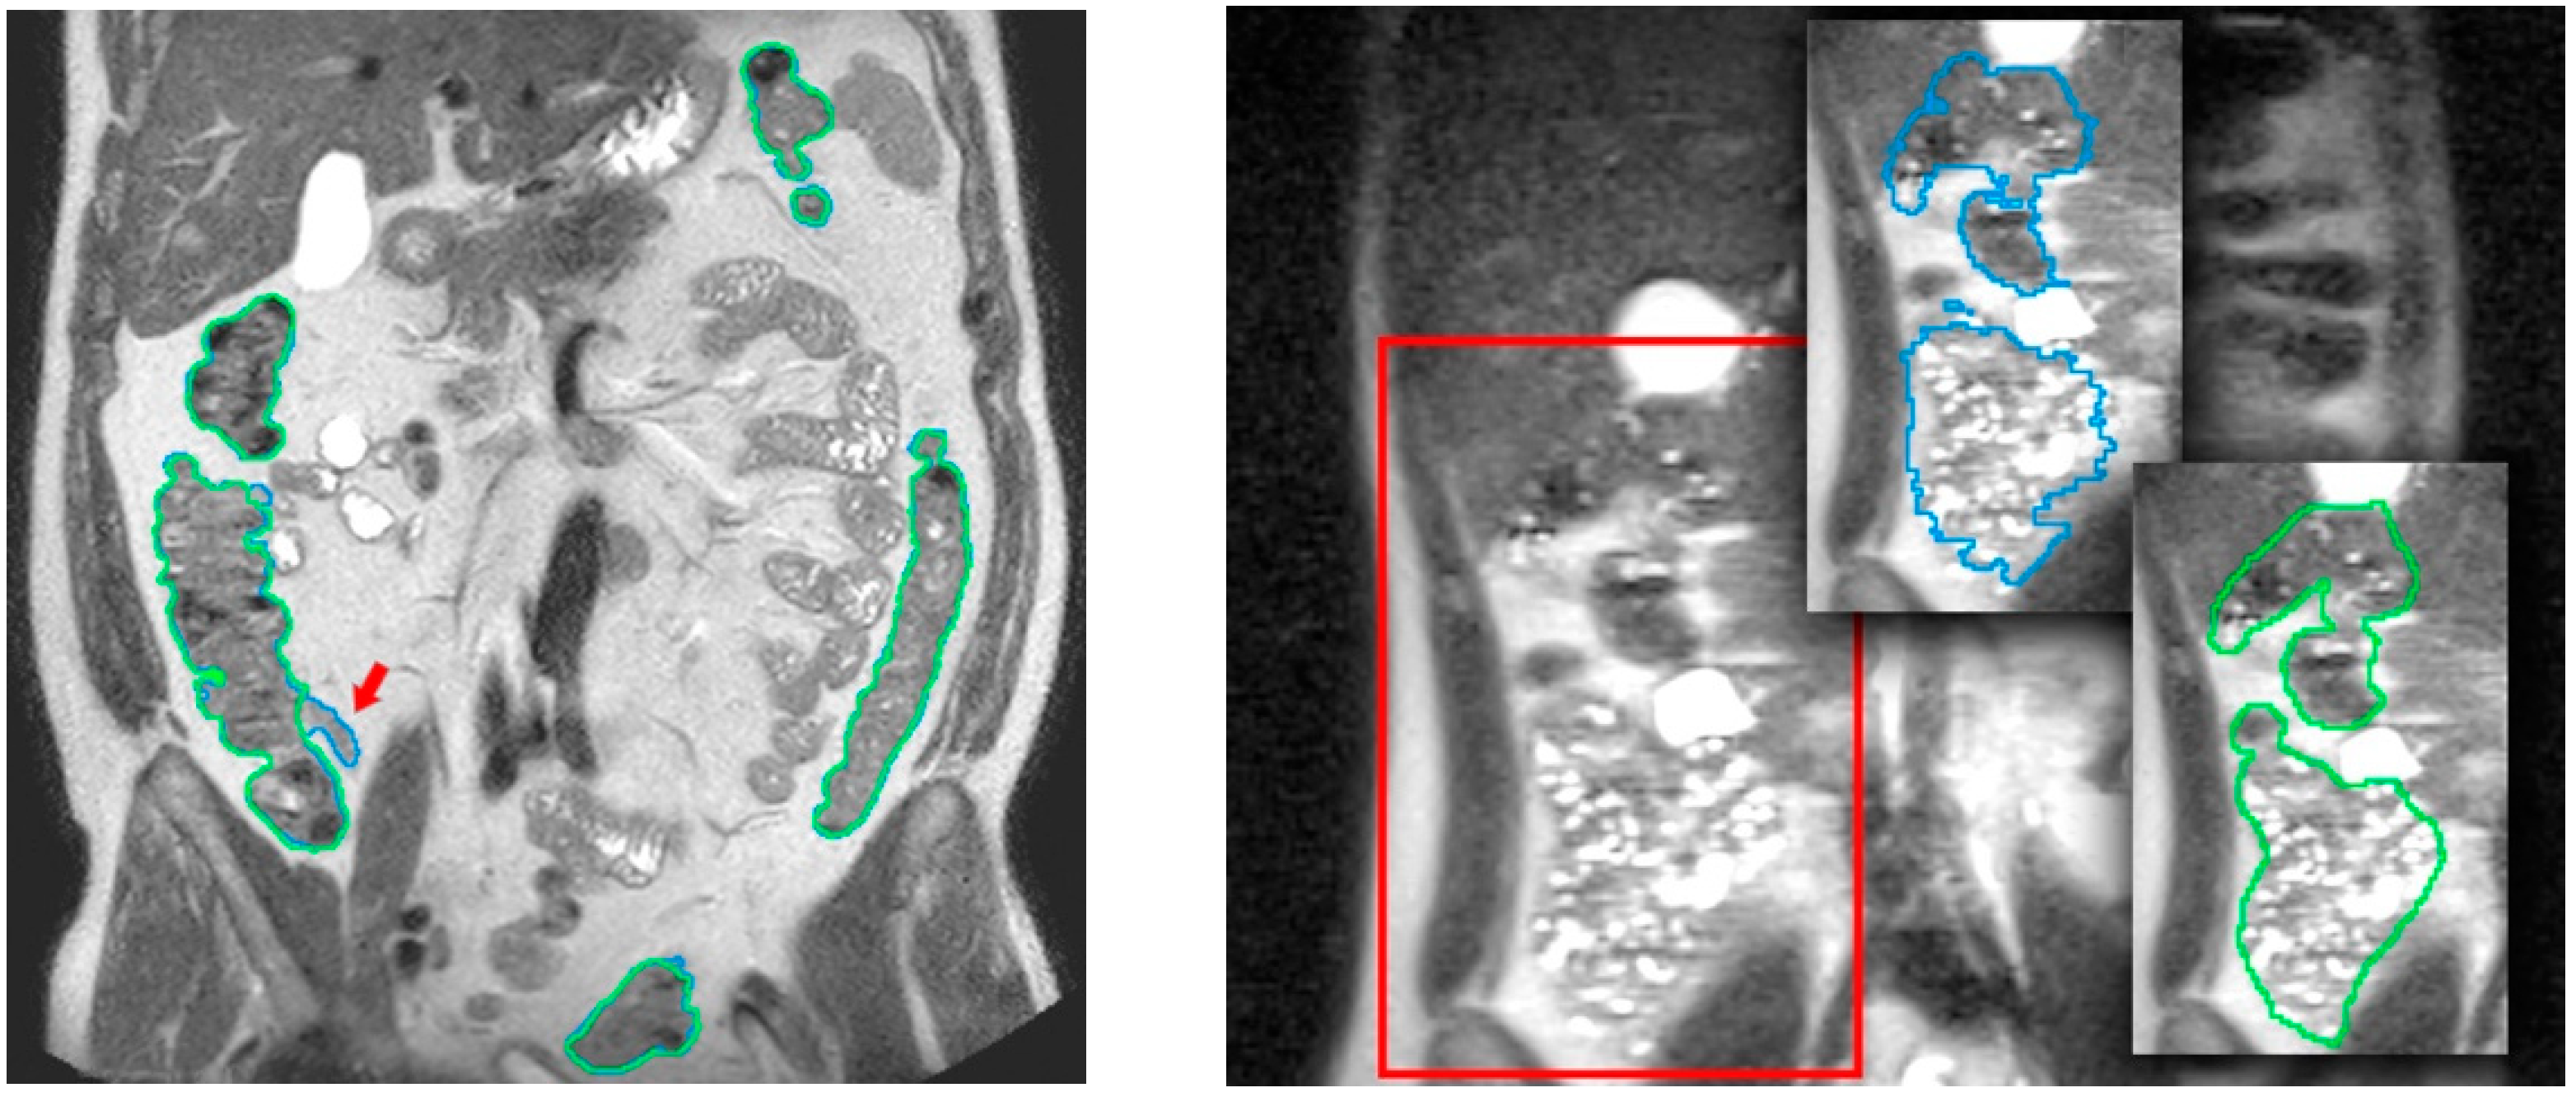

Regarding the validation of the colon segmentation in T1-FS images, the algorithm accuracy was evaluated by comparing the automatic segmentation results to manual segmentations of the colonic fecal content (taken as ground truth) performed by the specialist (in [15] the validation experiments were presented). Note that the specialist only segmented the fecal content because the complete segmentation was too demanding and almost impossible in areas where no fecal content was presented (areas with gas).

In total, 90 scans obtained from 35 healthy volunteers (8 women, 27 men; 20–28 Kg/m2 body mass index range) were used. The quantitative validation metric, named R, was defined as the percentage of ground truth fecal content inside the colon segmentation result. The achieved accuracy was (μR = 96.2%, σR = 4.2), demonstrating its viability for clinical usage (see Figure 5). The mean execution time was 9 min without any human intervention.

Figure 5.

Comparison of segmentation results in a T1-FS coronal slice. In the left image, the original slice visualized with the corresponding automatic colon segmentation outlined using a different color for each of its segments. In the right image, the same coronal slice is visualized with the corresponding manual identification of the fecal content, used as a ground truth in the validation process.